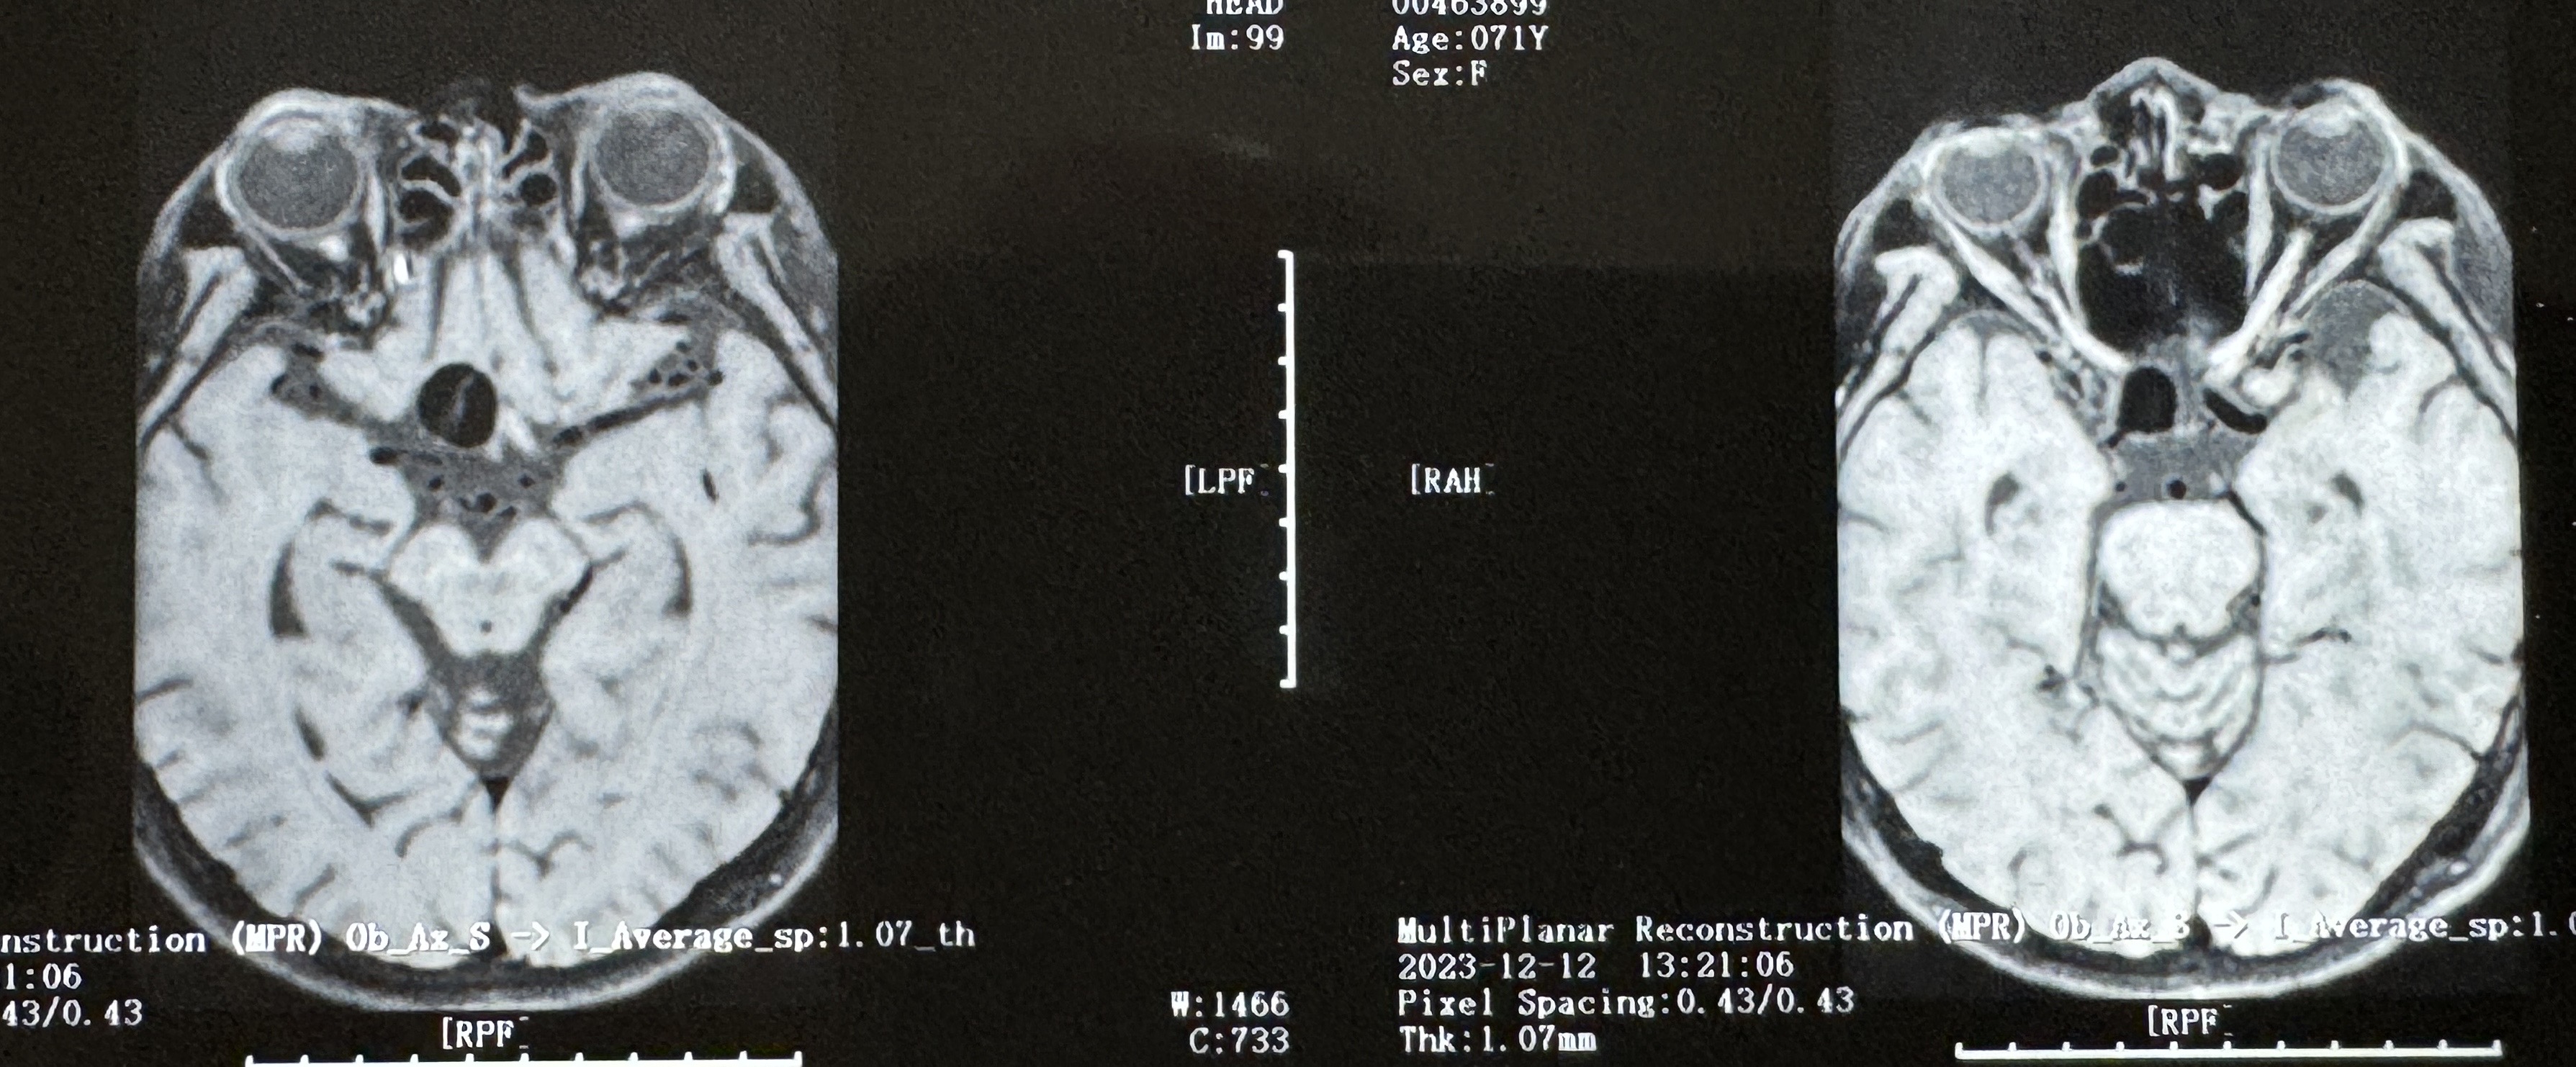

辅助检查;2023-11 外院 头颅MRI+MRA:左侧颈内动脉C6段动脉瘤;

2023-12-08 复旦大学附属华山医院 全脑血管造影:右侧颈内动脉C6段动脉瘤,瘤颈6.68mm,动脉瘤大小13.28*12.34mm

2023-12-12MRI

2023-12-08外院DSA:右侧颈眼动脉瘤,约13*12mm大小,压颈试验显示左右向及后向前代偿可